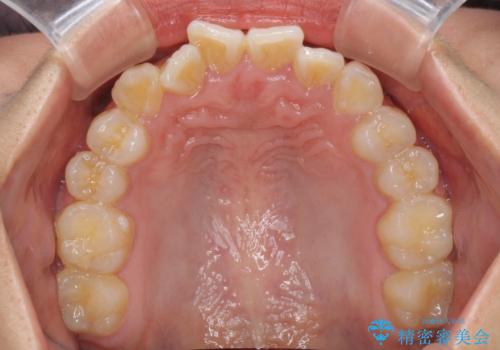

- 上下のデコボコと前歯のクロスバイトを改善したいとのことで来院された患者様です。

極力短期間で治療したいとのことで、ワイヤー装置による矯正治療を行うこととしました。

お住まいが遠方であったため、マウスピースによる矯正治療も提案しましたが、ご自身でのマウスピースの管理の面倒くささと、なるべく早く治療を終えたいとのことで、ワイヤー矯正を選択されました。